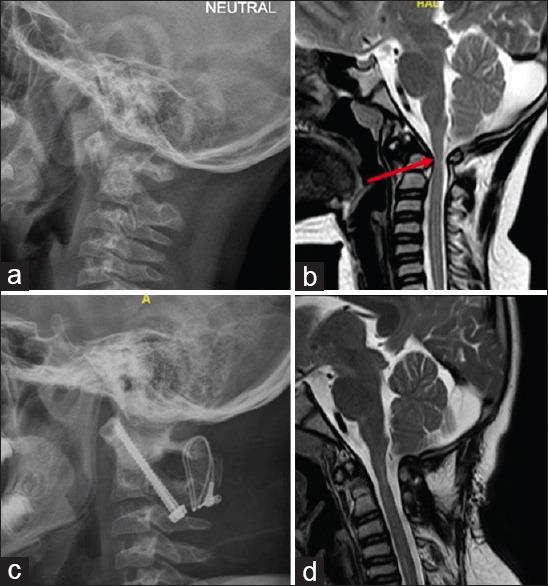

There were 4 males and 5 females (n = 9). The median age was 14 years (interquartile range [IQR]: 7-15.5). 77.7% (7/9) of patients had severe spasticity (Nurick Grades 4 and 5). The median duration of symptoms was 9 months (IQR: 5-39). The AAD was reducible in all (n = 9) cases. Eight (88.8%) patients had os odontoideum. The mean atlantodental interval (ADI) was 8.5 mm (±2.9). T2W cord hyperintensity was seen in 66.6% (6/9). Posterior C1-2 transarticular fixation was done in 8 and occipitocervical fusion in 1 patient. Follow-up of more than 6 months (7-57 months) was available in 8/9 (88.9%) patients. There was a significant improvement in spasticity (n = 8, mean Nurick Grade 1.7 (±1.1), = 0.003). Follow-up radiographs (n = 8) showed good reduction and fusion. A preoperative bedbound patient with poor respiratory reserve expired at 10 months following surgery. There were no other complications.

Posterior surgical approach for AAD in Down syndrome resulted in good alignment and fusion, with excellent clinical improvement. Patients with elevated PCO are poor surgical candidates and require home ventilation facility.